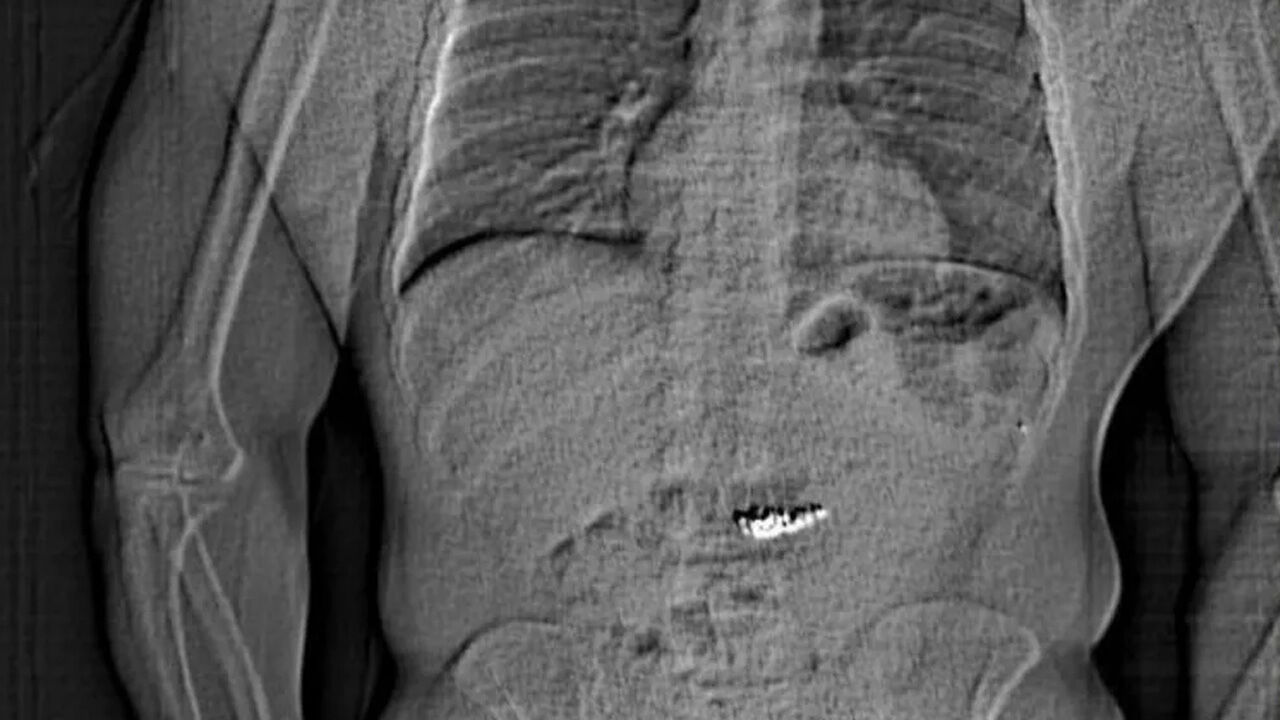

Gilder'ın röntgen muayenesinde çaldığı küpelerin midesinde olduğunun tespit edildiği kaydedilen açıklamada, hırsızın günlerce hastanede gözetim altında tutulduğu vurgulandı.

Açıklamada, hırsızın vücudundan doğal yollarla çıkarılan küpelerin yetkililer tarafından teyit edildikten sonra mağazaya teslim edildiği bilgisi paylaşıldı.

(Fotoğraflar: Orlando polisi)